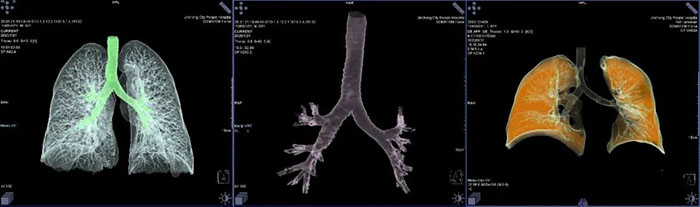

西门子SOMATOM Drive双源CT具有超高的扫描速度及时间分辨率,在全新Turbo Flash技术的支持下,完成全身动脉检查仅需3秒,冠状动脉扫描更是无需严格限制心率。对于胸部肺动脉扫描检查,扫描时间不到1秒,可以得到清晰的肺动脉图像,避免肺静脉干扰。完成2米范围全身动脉扫描仅需3秒,即可得到清晰图像。全新0兆球管性能优异,可持续行大范围扫描,轻松应对双下肢动脉CTA检查。

西门子SOMATOM Drive双源CT配合强大的Syngo.Via智能工作站可实现更高级的临床应用;肿瘤分割技术可对肺、肝、淋巴结以及其它各部位组织病灶实施一键式自动分割 ,自动测量,并且提供多种重要的肿瘤学参数。为检查定性,手术、放化疗前后效果提供可靠依据,做到真正意义上的精准医疗。

西门子双源CT独创的Turbo Flash(大螺距)模式,其螺距能达到3.2,扫描速度高达73.7cm/s,可在1秒内完成胸腹大血管、头颈心一站式筛查。儿科及无法配合憋气的患者无需憋气,实现平静状态下肺部CT成像,图像清晰,扫描速度快,仅需1秒左右,且射线剂量低。